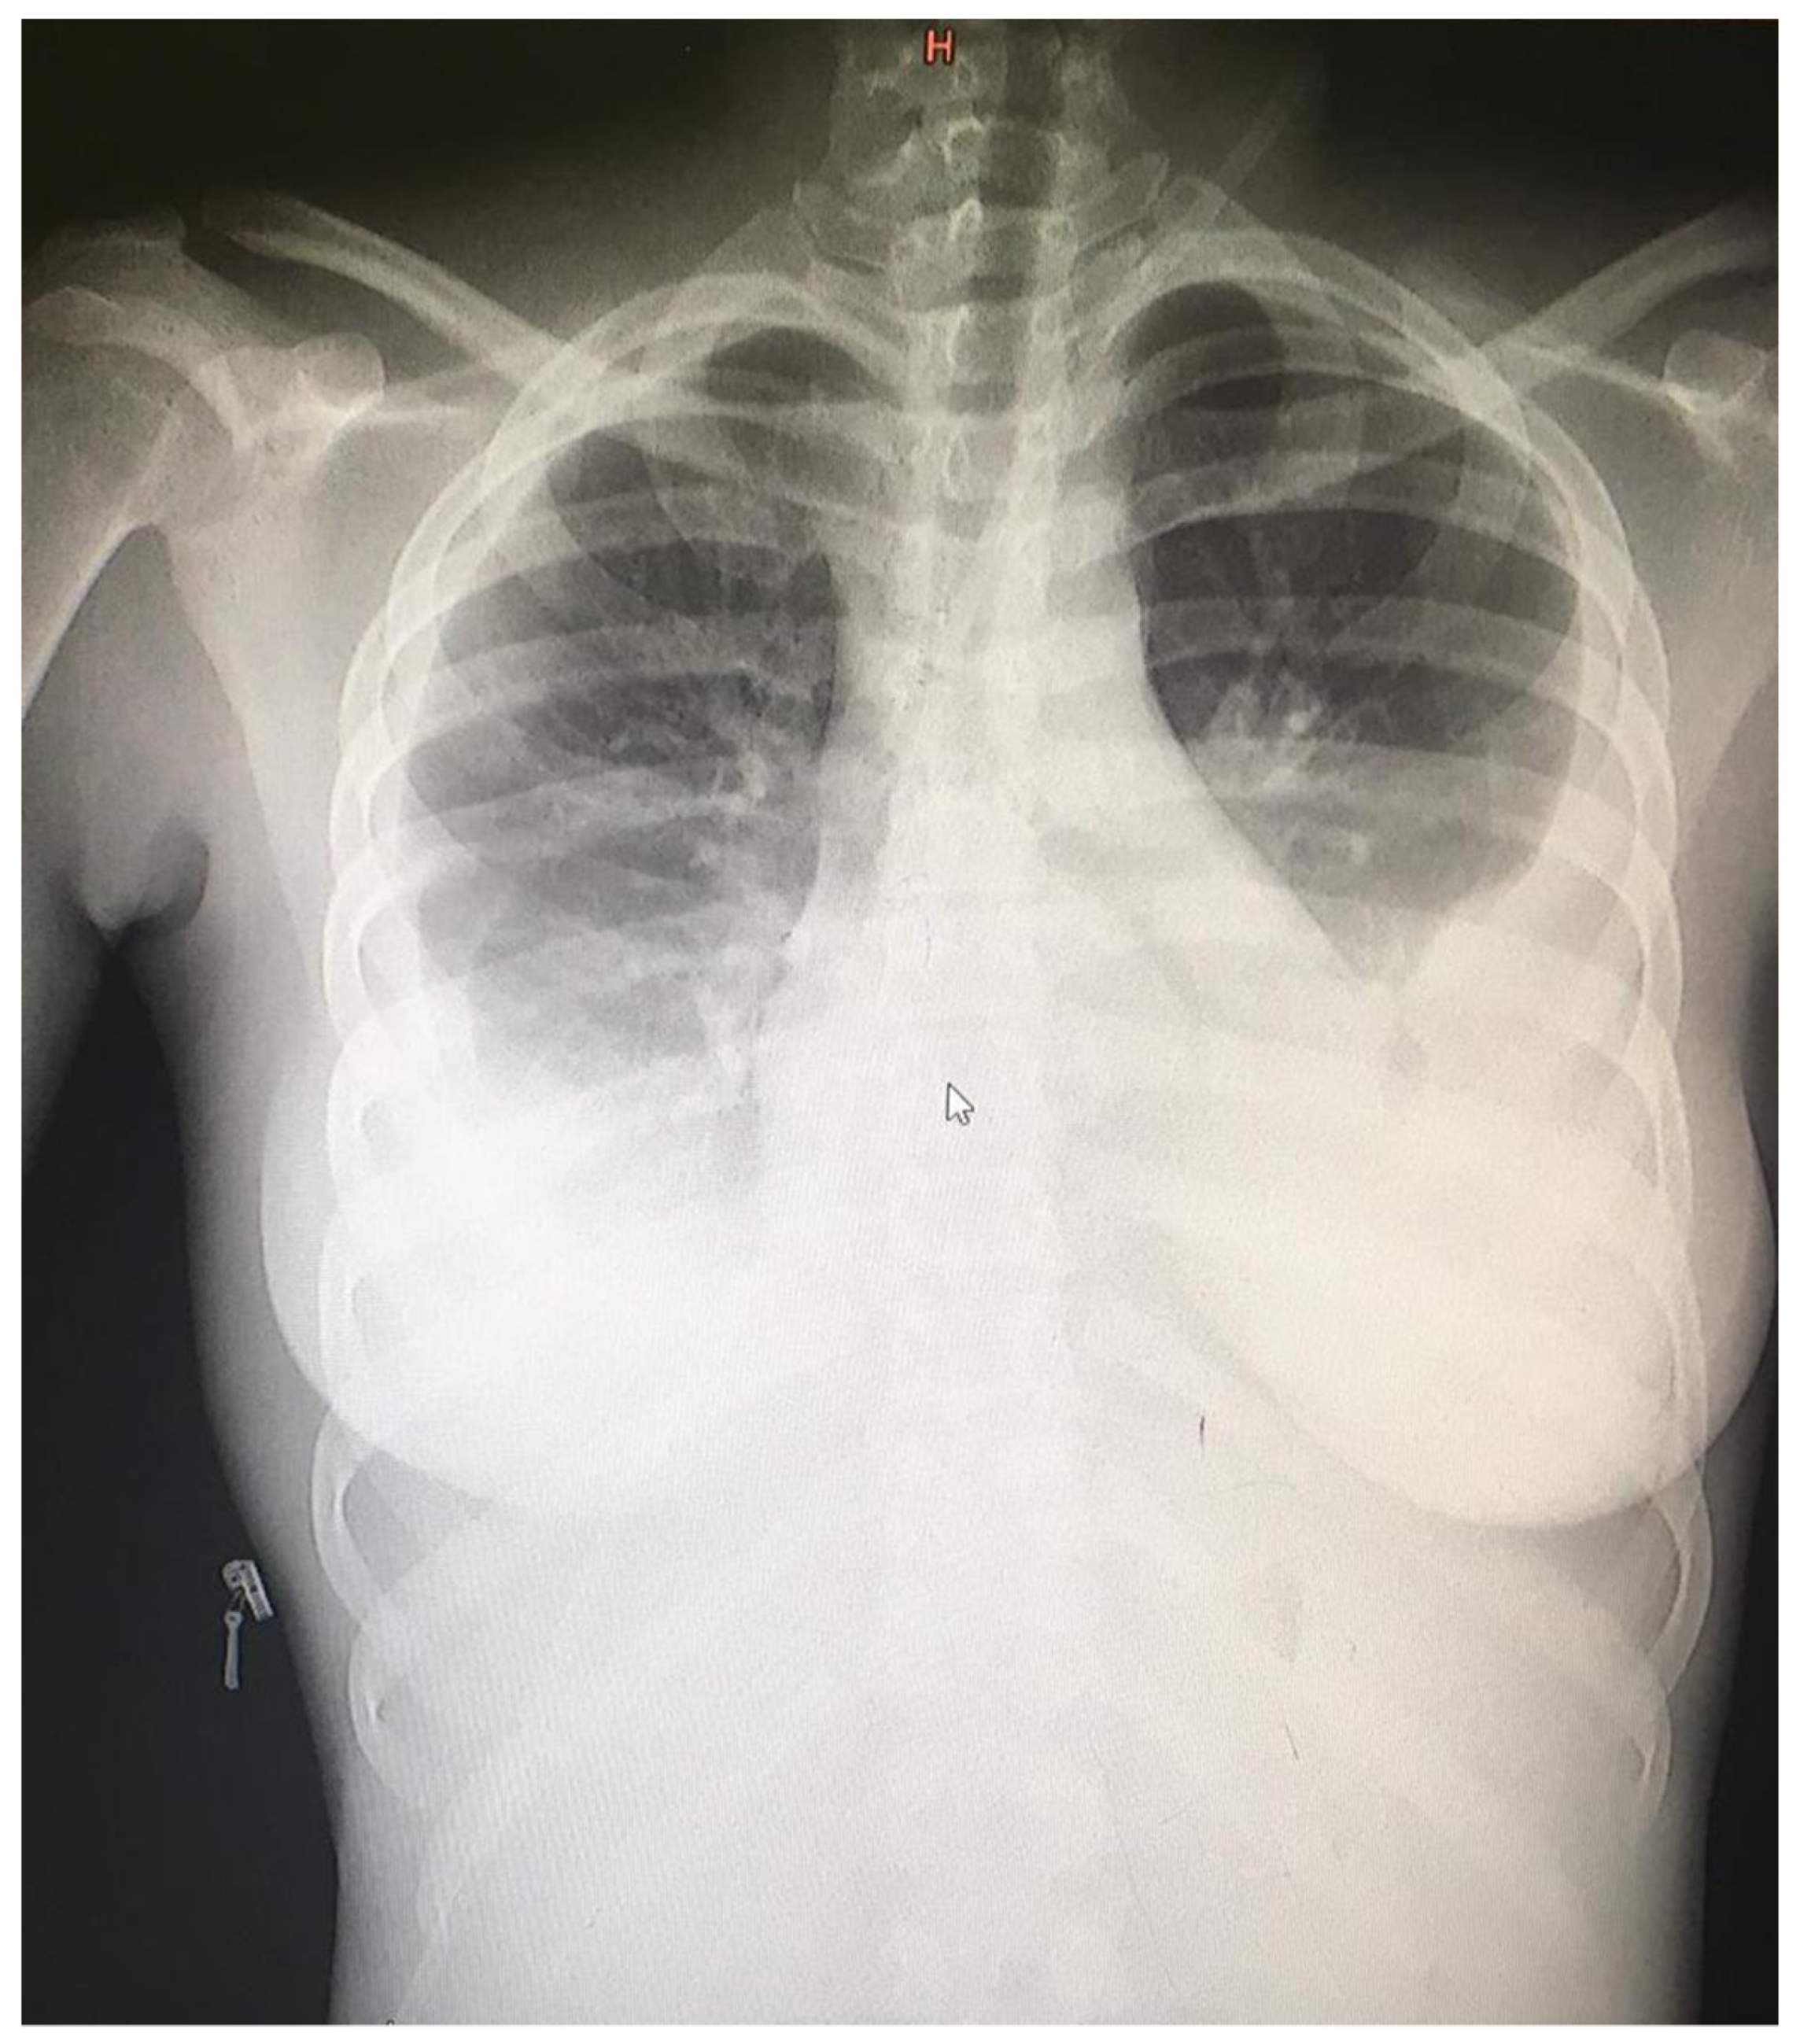

| Day 0 | Patient presented hypotensive and hypoxic. Left thoracentesis removed 2000 mL bloody fluid. Requiring supplemental oxygen started at 10 L/min via facemask. Received intravenous fluids, ceftriaxone 2 g, two units of blood. |

| Day 1 | Hemodynamics and respiratory status improved. Oxygen saturation 97% on 5 L/min. Received second dose ceftriaxone. KICS suspected. |

| Day 2 | Ultrasound revealed bilateral pleural effusions, pelvic free fluid, and hyperechoic splenic lesions consistent with disseminated KS. Right thoracentesis removed 1300 mL blood-stained fluid. Received first cycle of IV paclitaxel 100 mg/m2, IV dexamethasone 12 mg, third dose of ceftriaxone 2 g. |